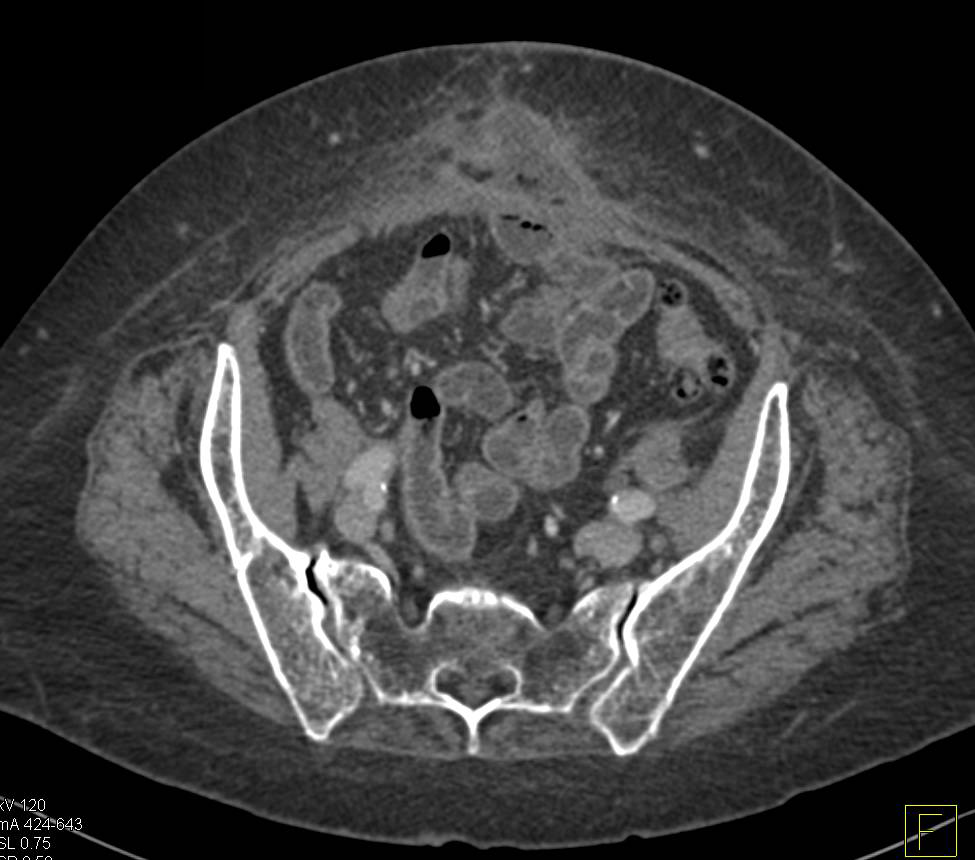

Pancreatic Cancer Obstructs the Duodenum at The Ligament of Treitz